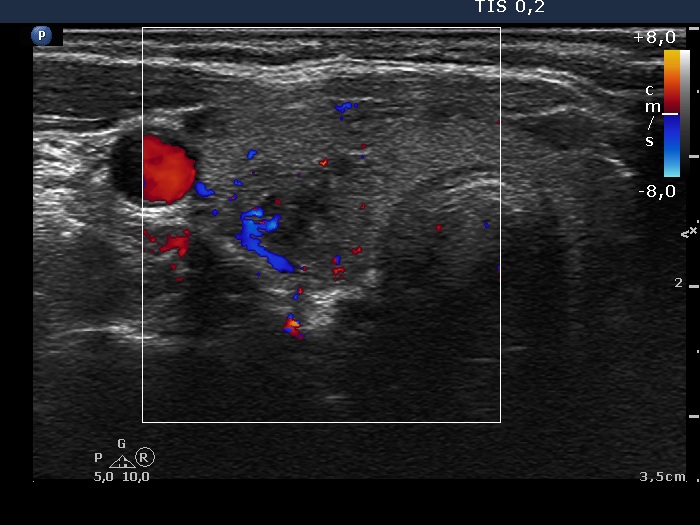

Right lobe, longitudinal scan

Right lobe, transverse view, color Doppler mode. The vascularization is not specific.